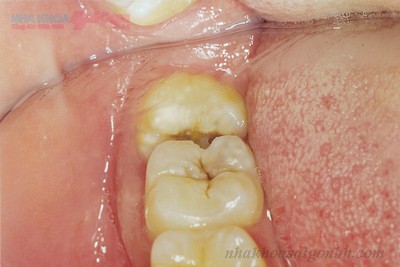

- Mọc lệch hoặc ngầm: Những chiếc răng khôn mọc lệch, ngầm hoặc nghiêng vào các răng bên cạnh khiến việc vệ sinh trở nên khó khăn hơn. Điều này làm tăng nguy cơ sâu răng và có thể gây ảnh hưởng đến các răng xung quanh.

Răng khôn sâu nặng: Khi răng khôn đã bị sâu nghiêm trọng, lan vào tủy hoặc tạo hố sâu lớn, bác sĩ thường sẽ chỉ định nhổ răng để ngăn ngừa các biến chứng như viêm tủy, nhiễm trùng, hoặc ảnh hưởng đến răng kế bên.

Răng khôn mọc lệch hoặc ngầm: Răng khôn mọc lệch, mọc ngang hoặc ngầm có thể gây nhiều biến chứng như viêm nhiễm, sưng đau, ảnh hưởng đến cấu trúc hàm. Trong trường hợp này, dù răng có bị sâu hay không, nhổ răng thường là lựa chọn tốt nhất để bảo vệ sức khỏe răng miệng.